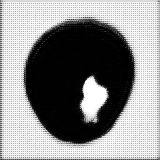

Main Module . The main module aims to generate two selective cuts, which separate the normal and abnormal information in an input image. The follows an encoder-decoder architecture like the U-Net, including one encoder and two decoders. The encoder extracts features of an input image , which could be an image located within or outside of the reference distribution , a collection of normal images. One decoder, the second upsampling branch, is designed to generate a “fence” cut that is constrained by an image fence formed by . The aims to generate an image and tries to fool the discriminator . The other decoder, the first unsampling branch, is designed to generate another “wild” cut , which captures leftover image content that is not included in . As a result, the produces another images to complement the fence-cut output . Since the wile-cut output is complementary to the fence-cut output, image information that can not be covered by the reference distribution would be included in the while-cut output, like the anomaly. The complementary relation between these two cuts and is enforced by a positive Dice loss, i.e., a “disjoincy” loss as discussed in the paragraph of Loss Functions. Figure 2 demonstrates the “disjoincy” of and , like their complementary histogram distribution and different thresholded images at different peaks.

Except for a weak guidance of the “disjoincy” loss for the “wild” cut, we adopt a reconstruction branch to make sure our two selective cuts include enough information to constrcut a coarse version of the original input. The reconstructor consists of a convolution layer with the Sigmoid as the activation function, which is applied on the concatenation of the two-cut outputs and to regenerate the input image back. This reconstructor ensures that the does not generate an image far from the input image and also ensures that the does not generate an empty image if the anomaly or novelty exists. Figure 3 shows the histogram separation of the reconstructed images, compared to the original input images which present complex histogram peaks and have difficulty in separating the brain tumor from backgorund and other tissues via a simple thresholding. The discontinuous histogram distribution of is inherited from the two generated sub-images and through a simple weighted combination. As a result, the segmentation task becomes relatively easy to be done on the reconstructed image .